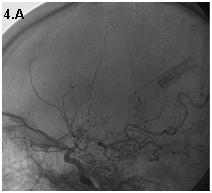

Mujer de 46 años que ingreso por cefalea súbita, hemiparesia izquierda y disartria, con tomografía axial computarizada cerebral simple que mostró hemorragia frontoparietal derecha drenada a ventrículos y arteriografía con patrón Moyamoya. Reingreso 3 meses después con deterioro del estado de consciencia y tomografía axial computarizada cerebral simple que mostró hemorragia intraparenquimatosa temporoparietal izquierda con extensión intraventricular y desviación de la línea media, se manejo en Unidad de Cuidados Intensivos con traqueostomía y gastrostomía, presentó neumonía y sepsis nosocomial, finalmente falleció en la Unidad de Cuidados Intensivos.